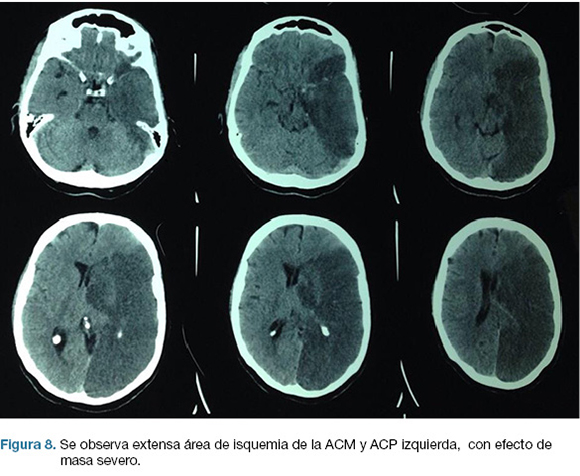

Se realiza TC de cráneo (Figura 7) y rTPA i/v. Ingresa a la unidad de ACV y a las 30 horas del inicio de los síntomas en forma brusca deprime conciencia e instala anisocoria a izquierda. Nueva TC de cráneo (Figura 8), surgiendo la indicación de intervención de emergencia.

En el post operatorio ingreso a CTI, IOT, en ARM, sin apertura ocular al llamado, gestos, flexión inapropiada de MSD. CGS: 6. De la evolución persiste con hemiplejia derecha y afasia severa. Escala mRS al alta: 5.